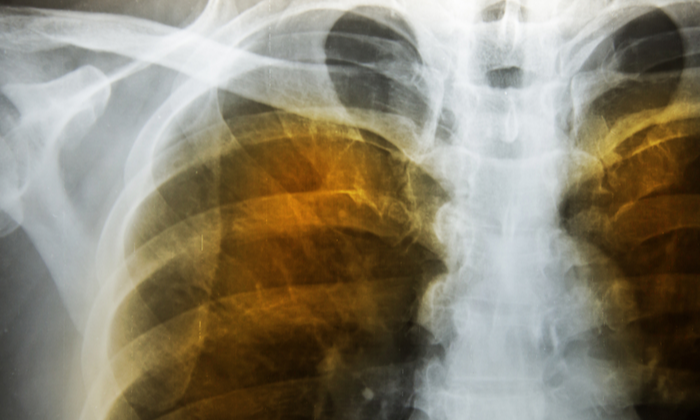

• ปอดเริ่มเป็นแผล มีรูพรุนอย่างเห็นได้ชัดเมื่อเอกซเรย์ออกมา